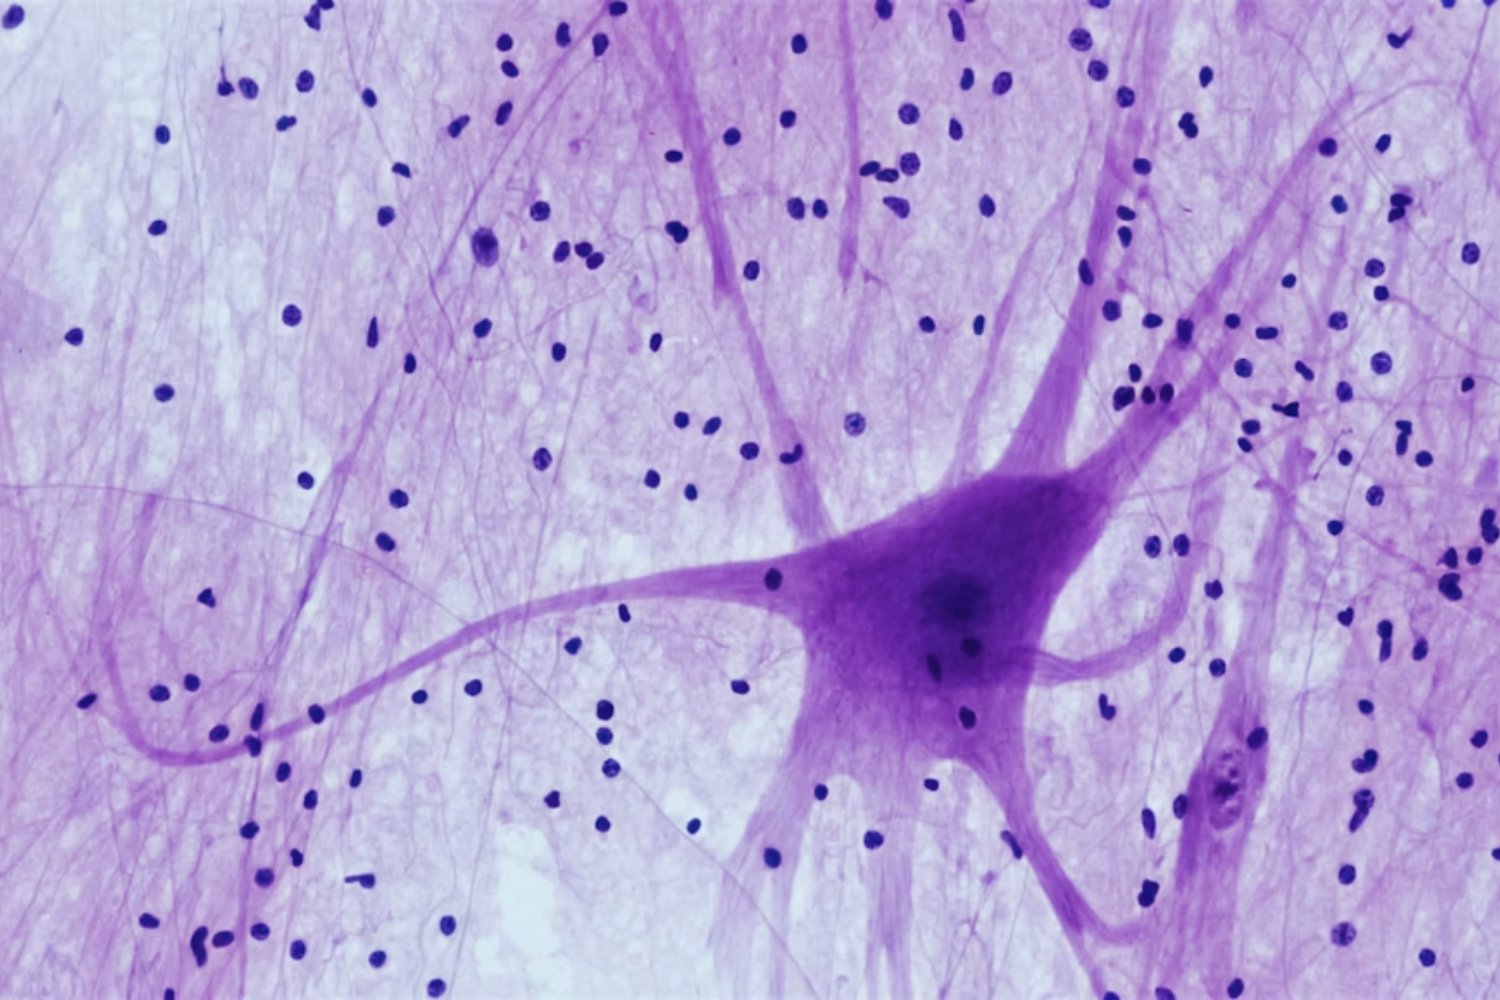

El conectoma: la clave de nuestros recuerdos

Los científicos están de acuerdo en que los recuerdos no son solo un proceso dinámico que se apaga con la muerte, sino que están almacenados físicamente en lo que se conoce como conectoma. Este término se refiere al conjunto único de conexiones neuronales que codifican nuestros recuerdos y nuestra personalidad. Sin embargo, a pesar de este consenso, aún hay desacuerdo sobre qué parte exacta del cerebro es responsable de almacenar la memoria, lo que plantea interrogantes adicionales sobre la recuperación de estos recuerdos.

Uno de los mayores desafíos en este campo es la preservación adecuada del cerebro. Técnicas avanzadas como la criopreservación estabilizada con aldehído, que combina vitrificación con fijadores químicos, podrían ofrecer una solución. Este proceso convierte el tejido cerebral en un sólido similar al vidrio, evitando el daño celular por formación de cristales. Aunque aún está en fase de desarrollo, este avance podría facilitar la preservación de recuerdos en cerebros humanos.